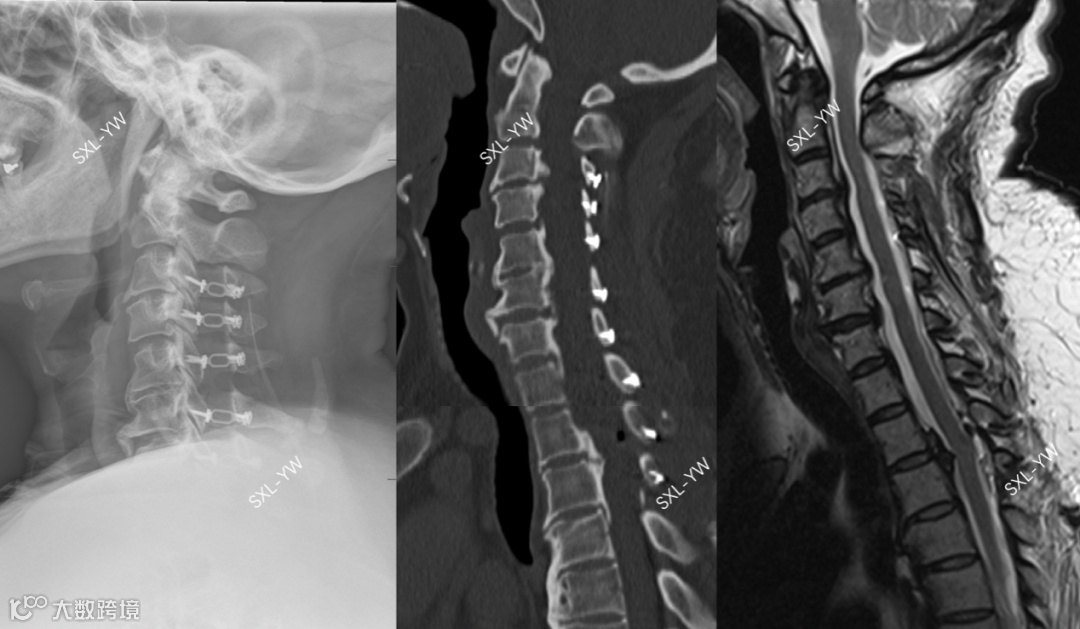

图12 K线与PCS评分的正面碰撞之一,术前影像

上述病例,如果参考K线理论,该OPLL患者K线阴性,单开门术后脊髓漂移将不充分、神经功能恢复将不理想,建议放弃单开门手术,行前路减压固定融合术或后路矫形内固定融合术。但是,如果参考我们的PCS评分,该患者得分15分,单开门术后神经功能恢复良好的可能性大,单开门手术的意义非常大。PCS评分建议手术节段为:C3-T1(得分区域)。

不同的指导意见,截然不同的治疗方法。采用K线做术前指导,患者需要接受创伤大、并发症多、后遗症多的融合手术。采用我们的PCS评分做术前指导,患者能接受到创伤小、并发症少、后遗症少的非融合手术。融合手术与非融合手术,该如何抉择?

图13 K线与PCS评分的正面碰撞之一,术后影像。C3-T1单开门术后脊髓获得充分漂移